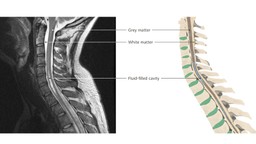

Rỗng tủy sống là tình trạng một hốc chứa dịch não tủy được gọi là ống tủy hình thành bên trong tủy sống của bạn. Bệnh gây ra nhiều triệu chứng đa dạng và dễ nhầm lẫn với các bệnh lý khác. Cần chẩn đoán nguyên nhân gây bệnh để có thể lựa chọn phương pháp điều trị phù hợp. Điều trị và quản lý các triệu chứng và bệnh tốt giúp bệnh tiến triển chậm và hạn chế các biến chứng nguy hiểm.

Rỗng tủy sống là một bệnh lý thần kinh mạn tính do hình thành hốc chứa dịch hình thành bên trong tủy sống của bạn. Hốc này có thể lớn dần theo thời gian dẫn đến tổn thương tủy sống, gây chèn ép và tổn thương các sợi thần kinh có nhiệm vụ truyền thông tin từ não đến các bộ phận bên ngoài và ngược lại.

Dịch não tủy là chất lỏng bao quanh và bảo vệ não cũng như tủy sống của bạn. Dịch não tủy cũng lấp đầy các khoang kết nối bên trong não hay còn gọi là não thất, sau đó tiếp tục dẫn đến một ống chạy dọc tủy sống của bạn.

Khi bạn mắc bệnh rỗng tủy sống, dịch não tủy sẽ tích tụ trong các hốc, giãn rộng ống trung tâm và tạo thành hốc trong tủy sống. Bệnh rỗng ống tủy rất hiếm, nó ảnh hưởng đến khoảng 8/100.000 người và chiếm tới 5 phần trăm các trường hợp bị liệt hai chân.